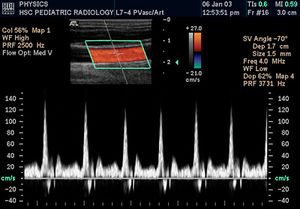

التخطيط الصدى الدوپلري

تكون الصورة عادةً ملونة، فيظهر الدم اما بلون أحمر أوأزرق حسب اتجاه الجريان بالنسبة للمجس الفاحص. ويقدم الجهاز معلومات ممتازة في تقييم صمامات القلب وارتفاع الضغوط الدموية في الأوعية الدموية.

| الجهاز القلبي الوعائي | To assess patency and possible obstruction of arteries Arterial sonography, diagnose DVT (Thrombosonography) and determine extent and severity of venous insufficiency (venosonography) | Intravascular ultrasound |

| طب الجهاز العصبي | for assessing blood flow and stenoses in the carotid arteries (Carotid ultrasonography) and the big intracerebral arteries | see Carotid ultrasonography. Intracerebral: see Transcranial Doppler |